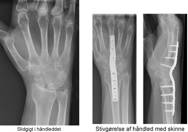

Stivgørelse af håndled

Stivgørelse er for mange personer en god løsning. I mange tilfælde er det angrebne led allerede blevet mere eller mindre stift inden operationen, så forskellen i funktion vil ikke blive meget ændret, men det er smertelindringen, der er gevinsten.

Efter stivgørelse af håndleddet kan du ikke bevæge håndleddet op og ned samt fra side til side. Drejebevægeligheden af underarmen og bevægeligheden af fingrene bevares.